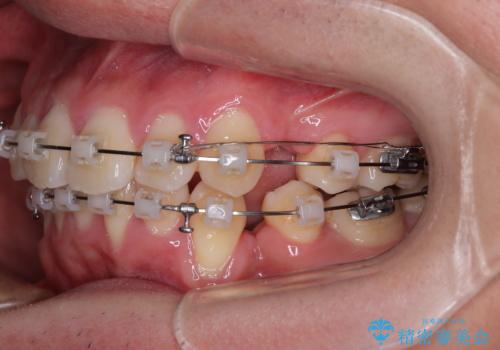

- クリアブラケット

- 1年6ヶ月

- 10-30回